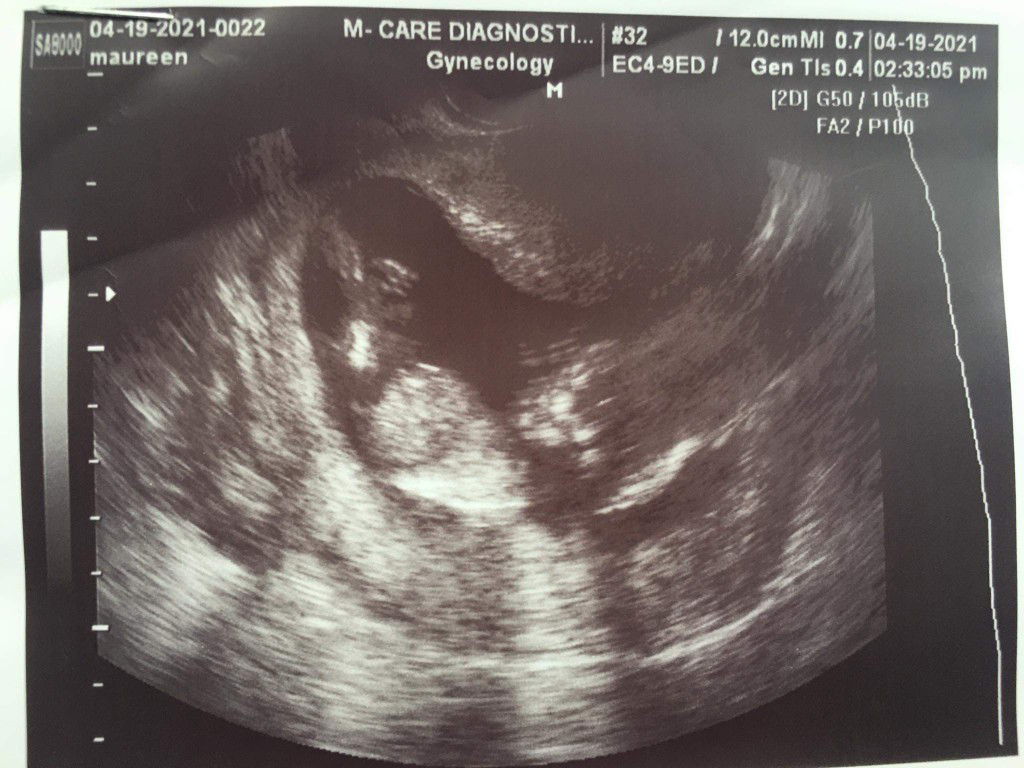

Sana Po my Mkapansin im 21week Pregnant po dapat ngaun pero 15weeks Prin c baby at d na lumaki tas patay na dw po cia Ask ko lng mga mommy anu po magandang inumin or Gawin para duguin para mailabas ko na cia masakit para sakin pero wla na kme maggawa ni partner Sana po Mapansin nio Salamat

ung 15weeks sis hindi na po dugo yan. baby na po sya.. so need ka na po iraspa. punta ka na po sa hospital para hindi na tumagal yan.

Nagpa check up kana ba sa OB? Paano po nasabing wala na si baby chineck po ba yung heartbeat nya at nag ps ultrasound napo ba kayo